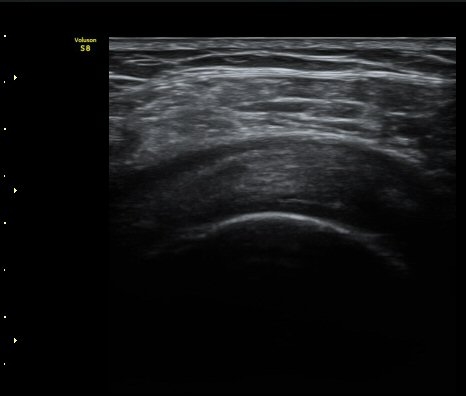

°üÀý³» ¼ö¾×Àú·ù´Â ¶Ñ·ÈÇÏÁö ¾Ê´Ù(±×¸² 3). ±Ø»ó°Ç Á¾´Ü¸é°Ë»ç¿¡¼­ Á¡¾×³¶³» ¼ö¾×

Àú·ù°¡ °üÂûµÈ´Ù(±×¸² 4, 5). ±Ø»ó°Ç Ⱦ´Ü¸é À­ ºÎºÐ¿¡¼­ °æ¹ÌÇÑ ¼ö¾×Àú·ù¸¦ º¸ÀδÙ(±×¸² 6).